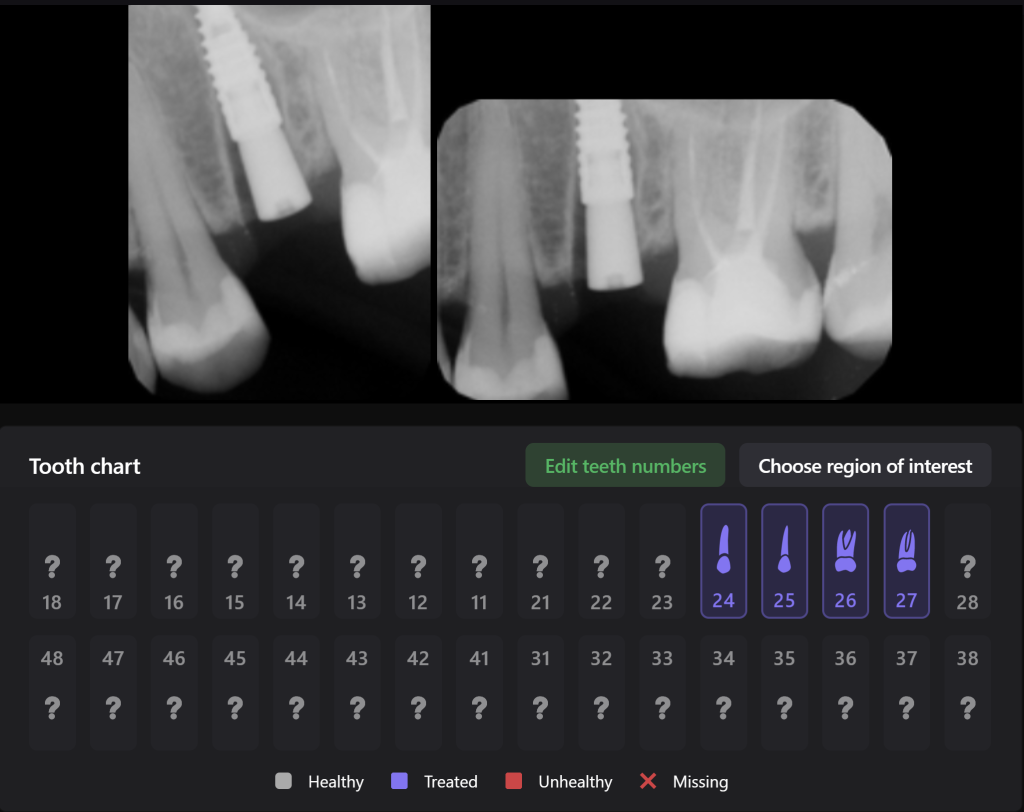

The planning of immediate implant placement using Diagnocat AI has many advantages for both the doctor and the patient. Let’s consider them using a clinical case example, in which the removal of tooth 25 (Universal 13) and subsequent implant placement were planned

The patient came with complaints that his dental crown on tooth 25 (Universal 13) fell out

In order to predict the prognosis of the tooth, data from the Diagnocat radiological report and visualization capabilities of the 3D-Viewer tool were utilized, in addition to a clinical examination